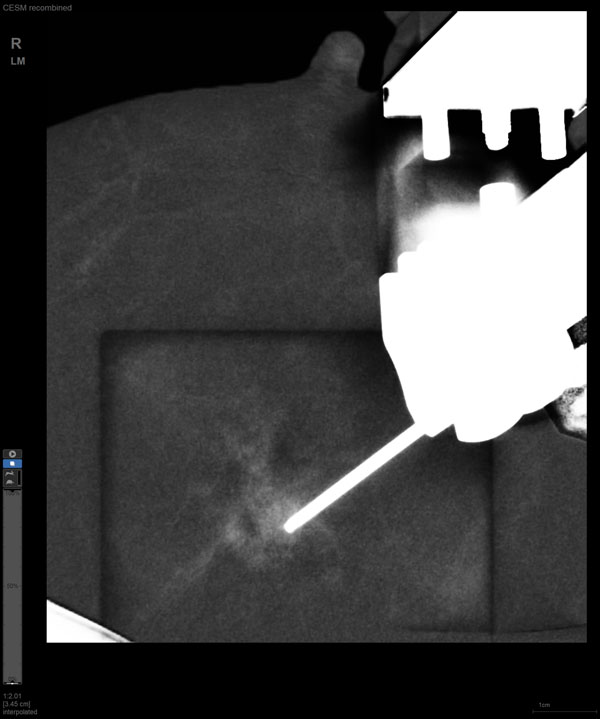

CEM引導下穿刺

某患者增強磁共振成像MRI顯示腫瘤周邊有活性,中心區域有組織壞死。為得到準確的病理結果,穿刺靶區需避開腫物壞死區域。在與患者主管醫生充分討論后,放射科醫生為患者行CEM引導下穿刺活檢術。術中,CEM檢查腫物同樣顯示為環形強化,巧妙避開壞死區域后,穿刺靶區選擇了腫物增強早期明顯強化區域,術程順利,僅用時15分鐘。術后該患者病理結果為浸潤性導管癌Ⅱ級。